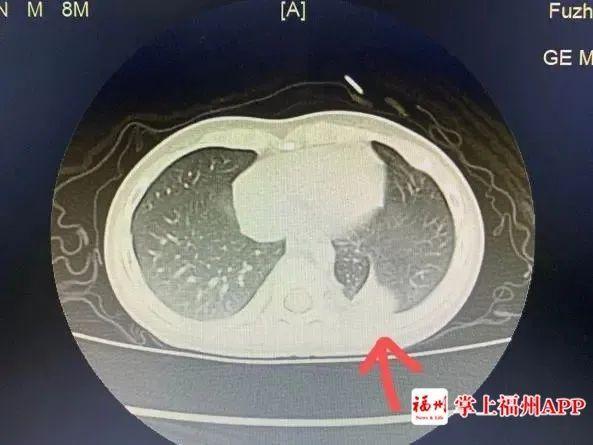

一个咳嗽这么难治愈吗?经过福建省福州儿童医院肺部CT检查,真相是小明的身体里“多了个肺”!!

医学上称为“肺隔离症”。

肺隔离症是一种先天性肺畸形,临床少见,其发病率约占先天性肺畸形的0.15% ~6.45%,一般无明显临床症状,多在合并肺内感染时与正常肺组织相通出现咳嗽、咳痰、咯血等症状,且反复发作,临床易误诊。

●增强CT结合三维血管重建发现异常供血可以确诊